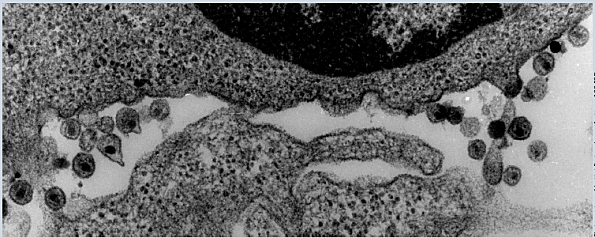

Primeras fotos del VIH

El profesor Charles Daguet, obtuvo la imagen de un nuevo virus

sirviéndose de un microscopio electrónico, la fotografía es tomada de la misma muestra extirpada

al joven francés.